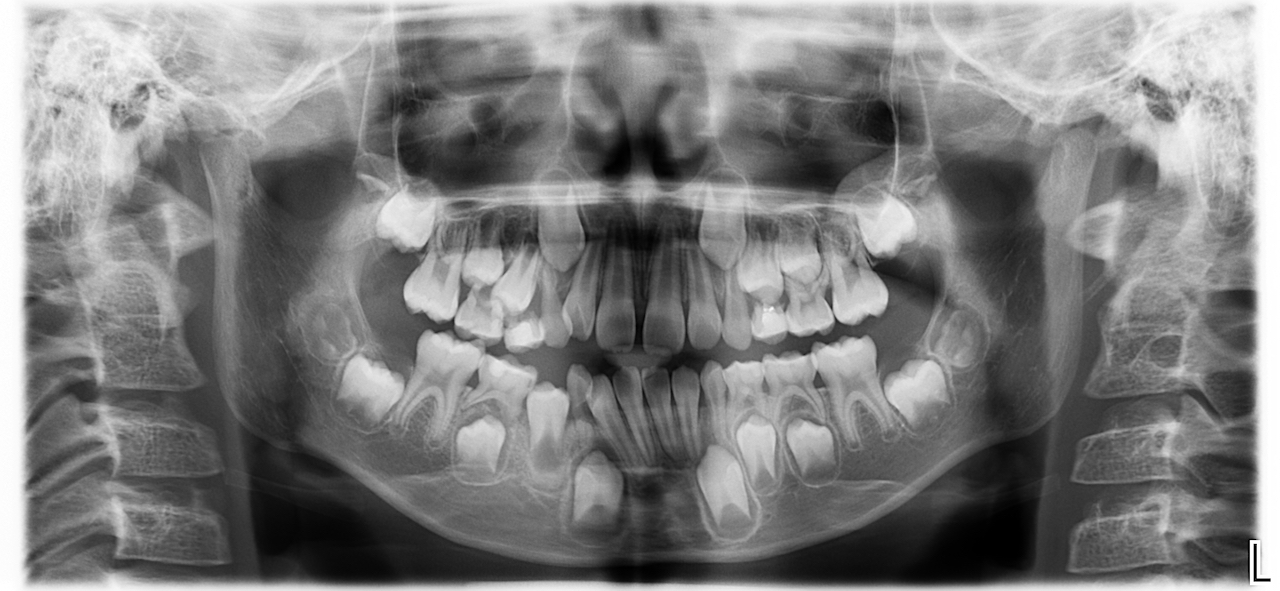

演示图片2

牙齿结构检测结果

自动检测牙齿结构

自动检测

AI自动识别曲面断层片中的关键解剖标志点

达到专家级别的解剖结构定位精度

秒级完成解剖结构识别和标注